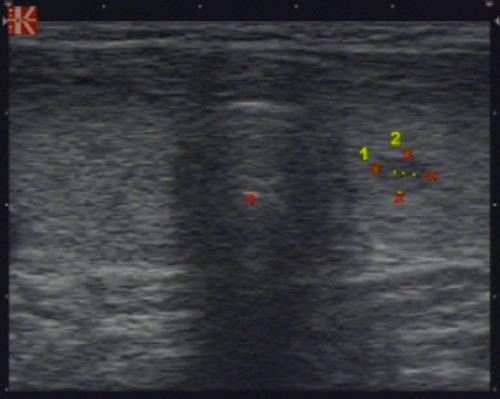

- Очаги с нарушением эхогенности – в норме отсутствуют. Но допускается присутствие единичных участков размером до 4 мм, которые возникают при увеличении фолликулов. Патологические уплотнения размером более 4 мм называют узлами.

Левая доля размерами 58 х 24 х 21 мм., объёмом - 14 куб. см, зхоструктура равномерно пониженной эхогенности, неоднородная за счет гипоэхогенного узла среднего сегмента размерами 6 х 5 х 4,5 мм., имеющего правильную округлую форму, ровные четкие границы, однородное внутреннее строение.